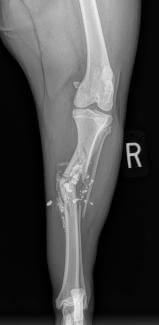

Pelvic Limb Fractures

Pelvis

Femur

Patella

Tibia/Fibula